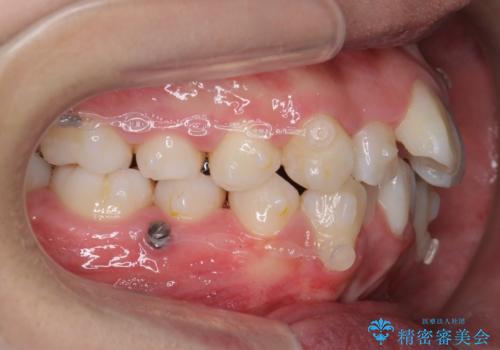

八重歯 抜かずにマウスピース矯正治療

- 八重歯を主訴に来院。

(2)奥歯を後ろに下げ、歯並びを拡大し、歯を少し削って抜かずにインビザライン矯正 矯正用ミニスクリュー併用 口元は下がらない

リファインメントもなく、1回で治療が終了しました。大変うまくいったケースです。

抜歯をしていないので口元は変わっていません。

八重歯も重症でなければインビザラインでも並びを歯を抜かずに整えることができます。